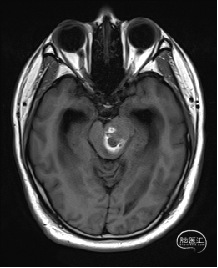

术前MRI检查

术前MRI检查提示左侧丘脑中脑海绵状血管瘤并卒中,梗阻性脑积水;

根据MRI及DTI显示,只有在丘脑与上丘之间的点(dot)进入病变才可能在切除病变时最大程度保护神经功能,由于上述原因,该“点”在术中显露极其困难,虽有导航指引,电生理监测的条件下,对术者的耐心、技术、经验及体能依然是极大的挑战;

术前详细的磁共振检查,包括平扫增强,SWI及DTI,可以规划出手术最适宜的路径及切入点;